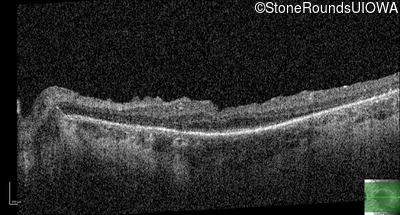

Optical Coherence Tomography - Left - 20/50 -2

Exemplar / OCT Stack